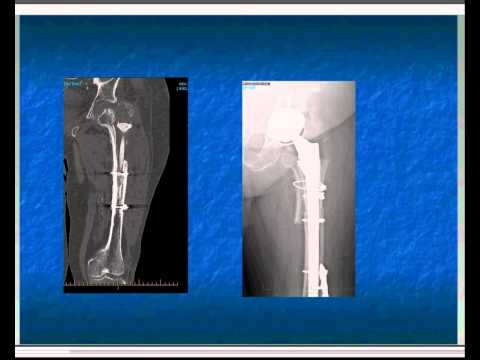

Talk about prosthetic joint infections (2 of 3)